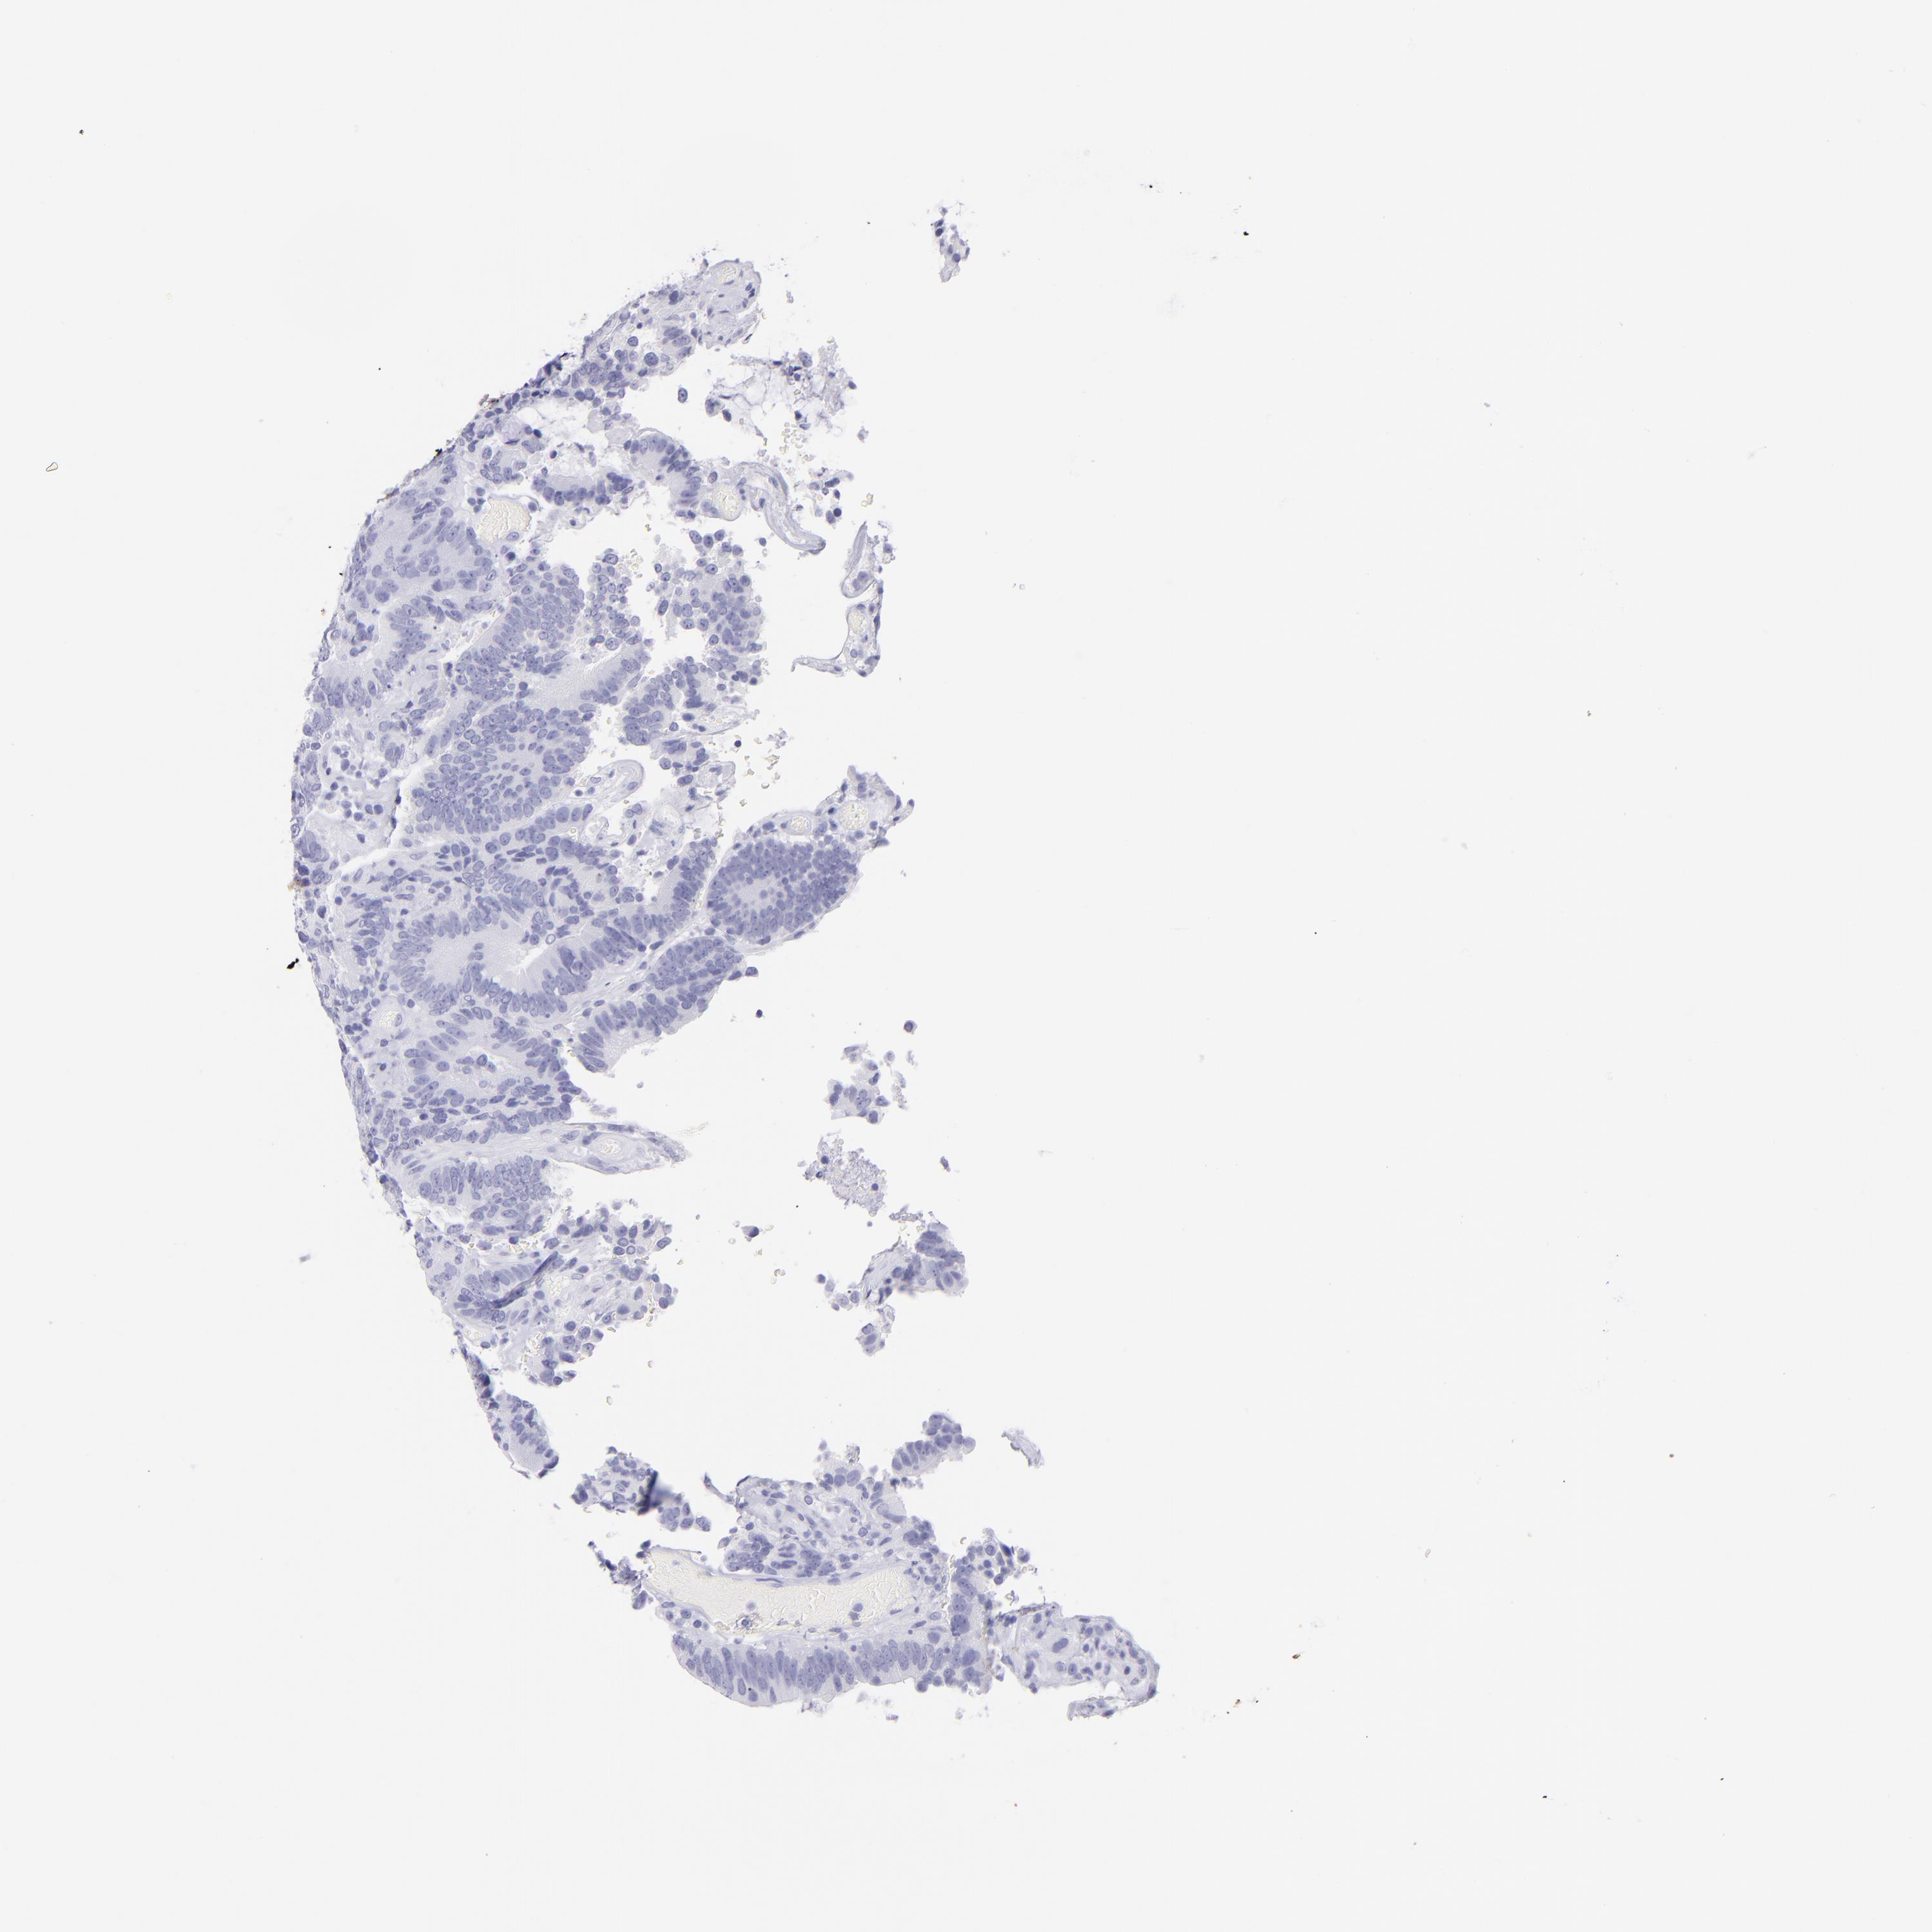

Colorectal cancer

Colon adenocarcinoma